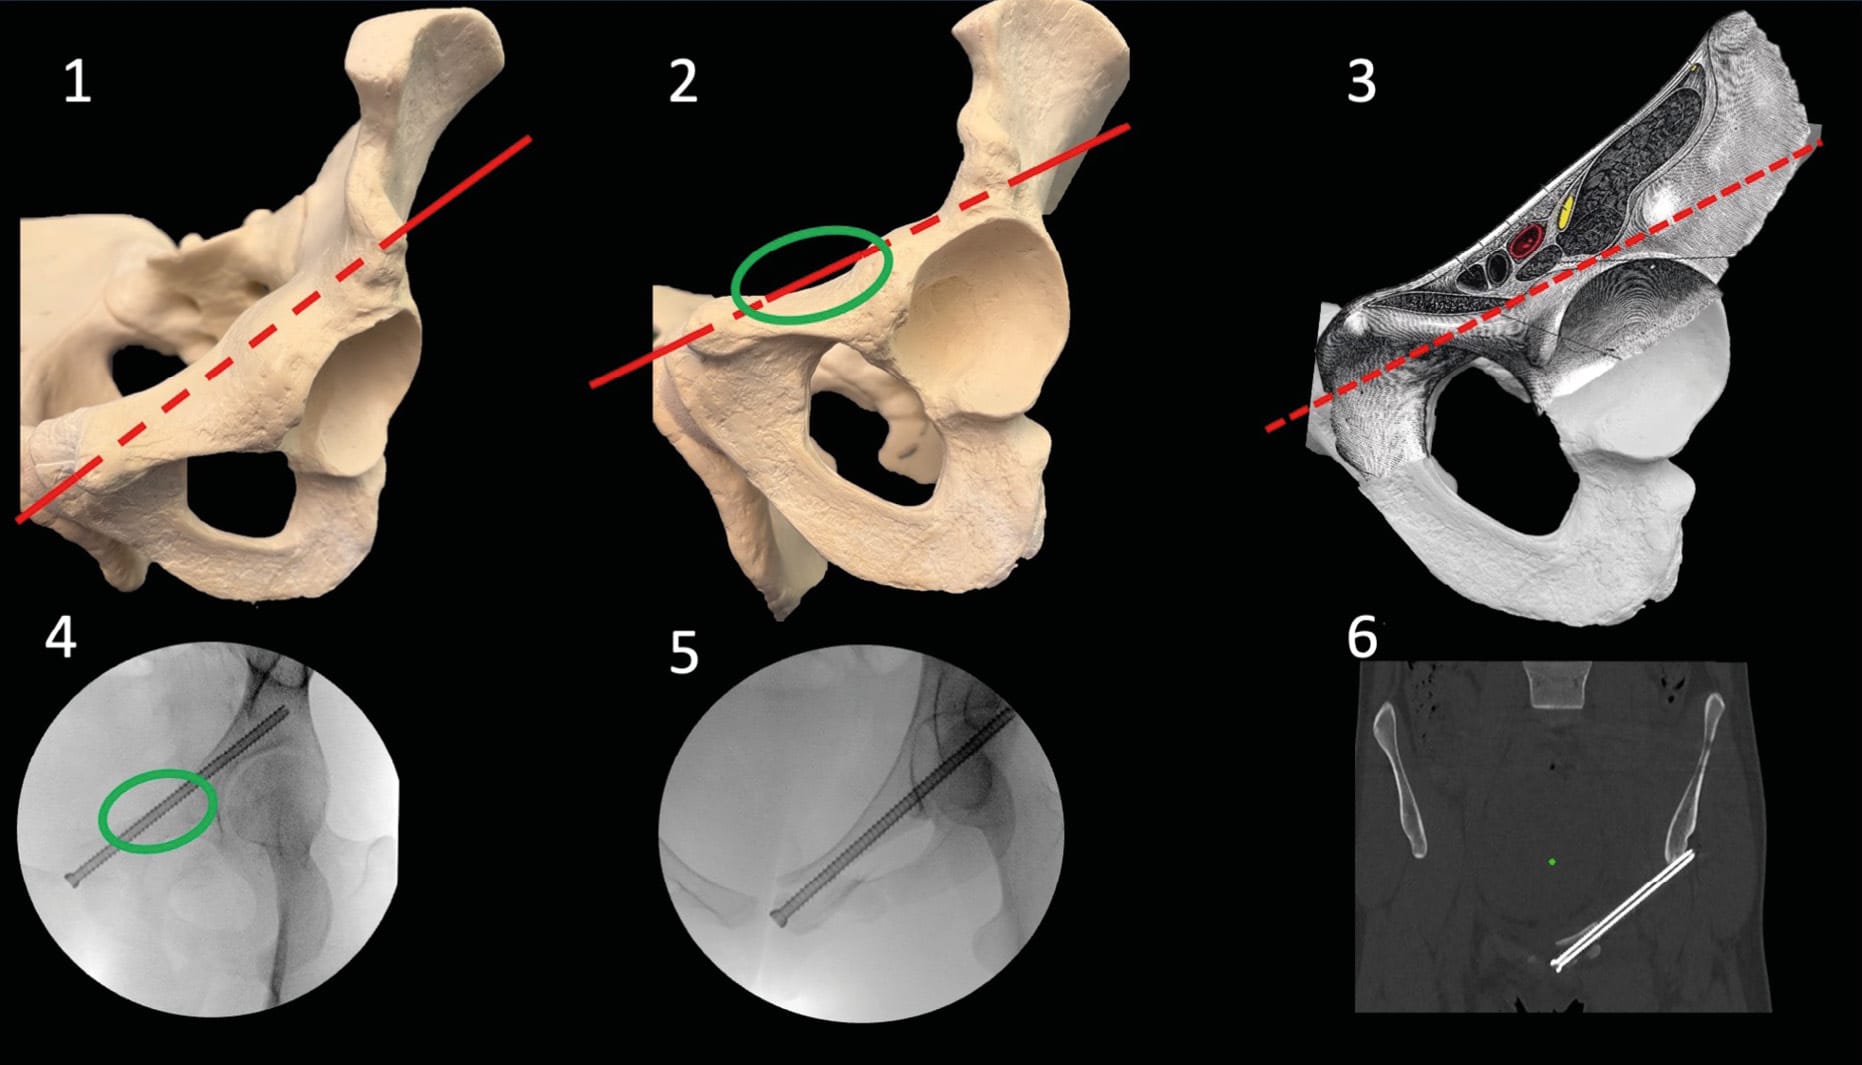

The hourglass-shaped bone corridor connects the anterior inferior iliac spine (AIIS) to the posterior superior iliac spine (PSIS). Several screw trajectories can utilize this corridor [19] Giannoudis PV, Tzioupis CC, Pape H-C, Roberts CS. Percutaneous fixation of the pelvic ring: AN UPDATE. J Bone Joint Surg Br 2007;89-B:145–54. https://doi.org/10.1302/0301-620X.89B2.18551.. Here, we will detail the most commonly used trajectory, which offers maximum safety.

Regarding imaging views, the "teardrop" view is frequently recommended in the literature. To obtain it, position the fluoroscope in Outlet and obturator oblique views (Figure 3), then adjust the angles to clearly isolate the base of the teardrop from the acetabular roof. In this view, the rays are adjacent to the major axis of the corridor, and the bottom of the teardrop represents the apex of the greater sciatic notch (GSN). Although this view is recommended, the authors do not recommend it and do not use it in their practice. Indeed, the bulk of the image intensifier limits freedom of movement, which complicates its use. We prefer a method based on using two orthogonal views, which offers better freedom of movement [20] Tosounidis TH, Mauffrey C, Giannoudis PV. Optimization of technique for insertion of implants at the supra-acetabular corridor in pelvis and acetabular surgery. Eur J Orthop Surg Traumatol 2018;28:29–35. https://doi.org/10.1007/s00590-017-2007-8. (Figure 16).

The AIIS entry point is visualized on a three-quarter wing view, which is very useful during the procedure to verify the absence of intra-articular breach and false passage through the greater sciatic notch, thus allowing trajectory management in the cranio-caudal plane. The guide wire progression within the corridor is monitored using an inlet view plus three-quarter obturator view (or "bottom wing" view according to Anglo-Saxon literature), which provides visualization of the internal and external tables of the corridor to manage trajectory convergence, as well as the AIIS. (Figure 16)

Finally, a true lateral view is useful to control the final screw length if the fracture requires complete corridor fixation. The "teardrop" view can potentially be performed at the end of the procedure for final verification.

The patient is typically positioned supine for antegrade fixation, but retrograde fixation can be performed in prone position if reduction requires posterior crest approach. Surgical draping has no particular requirements but must allow access to the root of the thigh.

For antegrade fixation, the starting point is located on the AIIS and thus not palpable. Typically, it is located two fingerbreadths caudally and one fingerbreadth medially from the Anterior Superior Iliac Spine (Figure 16). A teardrop view can be helpful to locate the skin incision. The enthesis of the direct head of the rectus femoris muscle on the AIIS can make proper guide wire positioning challenging. The guide wire is placed at the entry point using a three-quarter wing view, and the trajectory is adjusted to pass above the acetabulum and above the GSN. A trajectory adjacent to the apex of the GSN will allow maximum screw length implantation while remaining in the safest zone.

Then, the image intensifier is positioned for inlet plus three-quarter obturator view to manage trajectory convergence. The guide wire is then advanced through the corridor, alternating between these two views to check for absence of false passages. Once the guide wire is advanced to the desired position, a teardrop view is performed to confirm proper positioning within the corridor. A lateral view verifies the length. Subsequently, a screw of the desired length is inserted.

For retrograde fixation, the patient is positioned prone, the posterior iliac spines are easily palpable clinically, and the procedure is the same as for antegrade fixation. A 7.3 mm or 8 mm screw is typically used, with partial or full threading depending on the fracture pattern and proximity to the joint.